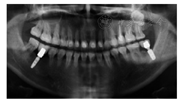

面像全口过渡性修复体戴用3个月后,再次与患者确认功能和美学效果无异常,按右侧后牙、左侧后牙、上下颌前牙的顺序,分3个区段行最终修复,17、27、36、47设计铸瓷高嵌体,余牙为铸瓷单冠修复。修复后前牙牙冠宽长比例适当,前牙美学、唇齿关系恢复理想(图6);覆

覆盖正常,牙尖交错位咬合稳定,前伸运动时由上下颌切牙引导,侧方运动为尖牙保护

。曲面体层X线片示修复体边缘密合无悬突(图7)。